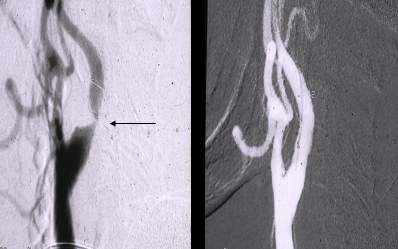

Figure 6. Crural PTA. Left panel: the only crural vessel filling is the peroneal artery; the posterior tibial artery is filled only in the proximal segment; the plantar arch in its continuation is also filled. Middle panel: successful recanalisation of the posterior tibial artery was performed using the guidewire (dashed arrow). Right panel: following balloon dilation, posterior tibial artery is well filled (arrows).

Due to technical reasons (antegrade or retrograde puncture, contralateral or ipsilateral puncture, femoral or brachial puncture), prognosis and risks, three types of levels are distinguished: iliac (Figure 4), femoro-popliteal (Figure 5) and crural (infragenual) (Figure 6) endovascular therapy. The latter two composes the infrainguinal group. PTA and stent placement are usually technically easier (with the exception of long occlusions), have a longer patency and carry lower risk in the iliac group compared to the other two groups. Patency following crural PTA is the worse and carries the highest risk, therefore, it is usually indicated only in Fontaine stages III and IV. The number of amputation per capita in Hungary is larger than that in most other European countries. In patients with gangrene and diabetes mellitus, crural PTA may save a large number of amputations. In case of successful PTA, limb salvage rate is considerably higher than crural patency rate, since perfusion needed for a healing ulcer or gangrene is considerably higher than for the basic functions (collateral arteries may be sufficient for such purpose). Subintimal PTA is performed more and more frequently: when luminal recanalisation is technically not possible, intentional dissection is done using the hydrophilic guidewire along the occluded segment; then, distally to the occlusion, the guidewire is directed back to the normal lumen and a new channel is formed along the normal lumen–dissected channel–normal lumen route (Figure 5).